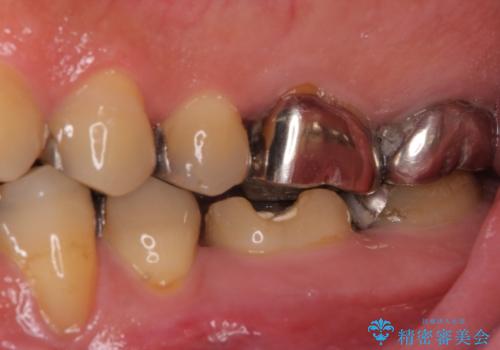

- 近医にてむし歯治療として根管治療を受けるも、痛みが全く改善しないとのことで来院された患者様です。

痛みが継続するため、「根管治療」と検索したところ、「ラバーダム」の重要性を知るところとなったようです。

根管治療を実施した後に、フルジルコニアクラウンにて補綴することとしました。

大臼歯の治療後に海外赴任され、数年ぶりに帰国されました。

奥歯に痛みがあるとのことで診察を行ったところ、海外(アメリカ)にて処置をした手前の歯が既に失活していることが分かりました。なお、治療を行った大臼歯はレントゲン写真上の治癒が認められました。

症状のあった歯に対しても根管治療を行い、同様に補綴治療を行いました。